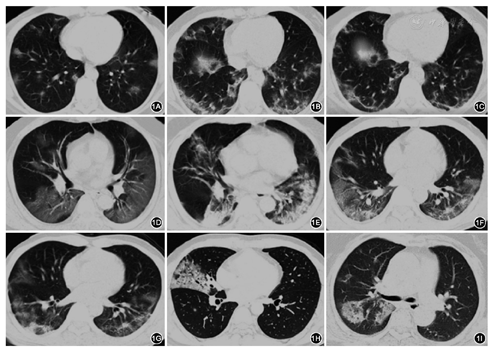

(1)免疫功能正常者病毒性肺炎:流感病毒感染可以群聚发病,表现为发热、干咳、肌痛和头痛,多数局限于上呼吸道感染。少数患者如儿童、老人、孕妇及有心肺等基础疾病的患者可出现病毒性肺炎。胸部影像学可见网状结节影,多发片状实变影,双下肺受累更多见(图2A、图2B)。H5N1高致病性禽流感肺炎,常迅速进展的大片实变。流感肺炎与新冠肺炎临床表现及影像学相似。呼吸道合胞病毒肺炎(RSV)儿童常见。RSV病毒肺炎常出现长程发热,影像学改变常见斑片影,沿支气管周围分布,可见肺不张和小叶实变,部分患者出现纵隔淋巴结肿大(图2C)。腺病毒感染多数表现为上呼吸道症状,有肺基础病患者(如慢性阻塞性肺疾病)可出现腺病毒肺炎。胸部影像学表现为弥漫的GGO或实变(图2D)。与新冠肺炎鉴别:①新冠肺炎早期及轻症与常见病毒患者临床表现及影像学表现相似,仅靠临床表现难以鉴别。临床怀疑病毒性肺炎的患者,在常规病原学筛查同时也需要进行新冠病毒筛查。②对于肺部病变迅速进展,短期出现呼吸衰竭,同时累及心、肾者,需多次、多部位标本送新冠病毒核酸检测,也可送新冠病毒IgM检测。同时考虑到少数情况下新冠肺炎合并呼吸道其他病毒感染可能性,也建议进行常见呼吸道病毒筛查。(2)免疫功能异常者病毒性肺炎:CMV肺炎患者常有人类获得性免疫缺陷综合征(AIDS)史,器官移植史以及使用大剂量糖皮质激素和免疫抑制药物史,病史对诊断有提示。胸部CT表现为双侧弥漫分布的GGO、密度不高的结节影、实变和网格影,其病变的边界常常欠清。影像学难与新冠肺炎鉴别(图2E)。

人类单纯疱疹病毒(HSV)肺炎在免疫缺陷,特别是人类免疫缺陷病毒(HIV)感染者和新生儿患者中相对常见。该病毒可以导致气管支气管上皮弥漫的溃疡,导致坏死性支气管肺炎,在影像学上与新冠肺炎有一定区别,确诊需要通过病毒学检测。与新冠肺炎鉴别:(1)呼吸系统症状严重程度与重症新冠肺炎相似,但较少在短期内出现心肾受累。(2)以往的基础疾病和用药史对诊断有一定的提示意义;(3)影像学检查、血常规及ESR、C反应蛋白等对诊断帮助不大,确定诊断需病原筛查。

(1)支原体肺炎:常见于5~40岁人群,典型症状包括乏力、发热、寒战、头痛、咽痛和干咳等,类似病毒性肺炎。多数患者呈自限性,胸部CT可表现为局灶或弥漫分布的支气管周围增厚,可见GGO及小叶中心性小结节(树枝出芽征,图2F),广泛的间质改变不多见。(2)衣原体肺炎:临床表现多样,可以无症状,也可出现呼吸衰竭和多器官受累,胸部CT表现多样,可以出现局灶实变,也出现间质改变,支气管壁增厚常见。(3)军团菌肺炎:是导致重症社区获得性肺炎(CAP)的常见病原体之一。患者常有污浊冷凝水接触史,也可群体聚集性发病,典型症状包括高热、寒战、乏力,常合并全身表现,如低钠血症、肝功能异常和消化道症状,对诊断有一定提示。其影像特征不同于经典的大叶性肺炎,常表现为多叶段的实变周围可见磨玻璃样渗出(图2G)。外周血白细胞和中性粒细胞计数增高,军团菌尿抗原和血清抗体检测有助于鉴别。

与新冠肺炎鉴别:(1)部分患者与新冠肺炎在临床及影像学上均难以区分;(2)疫情期间,为明确诊断,加强防控,可筛查病原学进行诊断及鉴别诊断。

(1)PJP:常见免疫功能缺陷患者,表现为高热,呼吸困难。影像学表现为弥漫的肺门为中心的纤细网格和边界欠清的GGO(图2H),小叶间隔增厚,如果不治疗,会迅速进展为弥漫均质的实变影,PJP更多以肺门为中心,而新冠肺炎更多从外周起病。PJP可出现多发或单发囊性病变,目前看到的新冠肺炎没有发现这个特点。与新冠肺炎鉴别:(1)呼吸系统症状严重程度与重症新冠肺炎相似,但较少在短期内出现心肾受累;(2)以往的基础疾病和用药史对诊断有一定的提示意义;(3)影像学检查与新冠肺炎有一定差异,但血常规、ESR及C反应蛋白等对诊断帮助不大,除进行已知咽拭子病毒核酸检测,还需要积极进行其他病原学检测,包括痰及下呼吸道标本肺孢子菌检测。

曲霉肺炎:免疫功能受损患者的曲霉感染在病变早期可以出现数个磨玻璃密度的结节影,曲霉肺炎病灶中心高密度,外周GGO的晕征多见(图2I),而新冠肺炎更多表现为密度均匀的GGO。与新冠肺炎鉴别:(1)与轻症新冠肺炎在临床及影像学上有时难以区分,既往病史、G试验和GM试验检测,在一定程度上有助于鉴别。(2)疫情期间,为明确诊断,加强防控,可筛查病原学进行诊断及鉴别诊断。